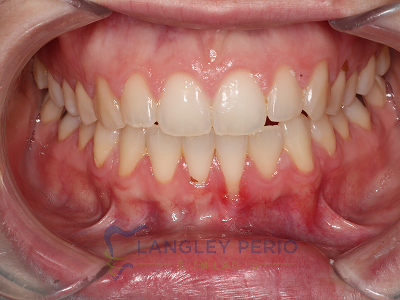

Case 3

Alloderm tissue grafting performed to improve root coverage and esthetics. This technique does not require tissue to be taken from the patient’s palate.